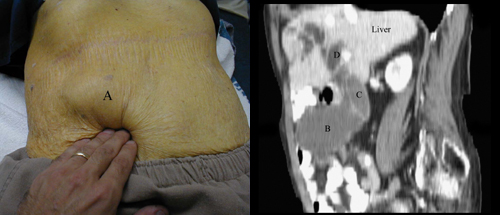

الحويصل الصفراوي المجسوس

سرطانة الأوعية الدموية أدت إلى توسع  و تمدد الحويصل الصفراوي عند هذا المريض و لهذا يمكن جسه بسهولة ( A ) . لاحظ لون الجلد الأصفر اليرقاني الناتج عن انسداد السبيل الصفراوي . الـ CT – يبين من خلال المقطع السهمي توسع المرارة ( B ) ، كذلك توسع القناة الصفراوية المشتركة ( C ) . و توسع الأقنية داخل الكبد ( D ) . إن متلازمة Courvoisier  تبدي نفس الموجودات عند مريض مصاب بسرطان البنكرياس .